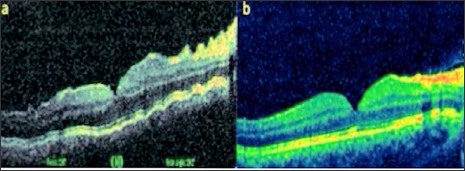

As a result of the examinations, traumatic cyclodialysis induced hypotoniamaculopathy was diagnosed for right eye. Topical corticosteroid and cyclopentolate therapy was initiated, and 3 days later the right eye axis was measured as 22,80 and the refraction rate was measured as +0,75. The IOP returned to 18 mmHg and the VA was 10/10. Comparing the OCT images taken at the end of treatment with the first received OCT, the choroid, RPE and wavy appearance of the retina (Figure 1a). Were seen to be healed at the end of treatment (Figure 1b). Cyclodialysis was detected in the temporal quadrant (Figure 2a). By UBM and normal culinary anatomy was obtained at the end of the treatment (Figure 2b). There was a normal appearance at the end of the treatment (Figure 3a), while significant increase in tortuosity was observed in vascular structures at the first examination of the FOF (Figure 3b).

Figure 1: Right eye view (a) at first examination and (b) post-treatment OCT images.